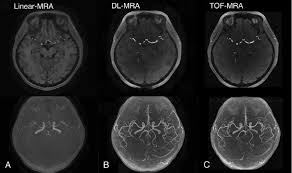

"MRA(Magnetic Resonance Angiography, 자기공명 혈관촬영)"는 MRI를 기반으로 혈관 구조를 영상화한 검사입니다.

- 원리: MRI 기술을 활용하여 혈류 신호를 강조하고, 혈관과 주변 조직을 분리하여 영상화

- 주요 특징: 동맥, 정맥, 혈관 협착, 동맥류 등 혈관 상태 평가에 특화

- 조영제 사용 여부: 일부 경우 가돌리늄 기반 조영제를 사용해 혈류를 더 명확하게 관찰

MRA는 심혈관 질환, 뇌혈관 질환, 말초 혈관 질환 등 혈관 이상 진단에 특히 유용합니다.